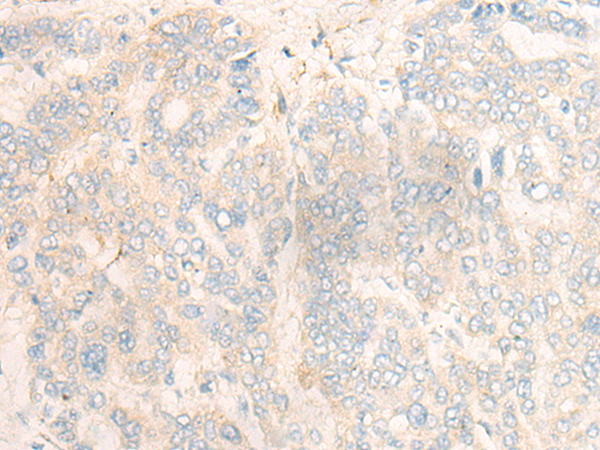

分类: 科研抗体货号: P06328别名: PAP1应用: WB,IHC反应种属: Human, Mouse